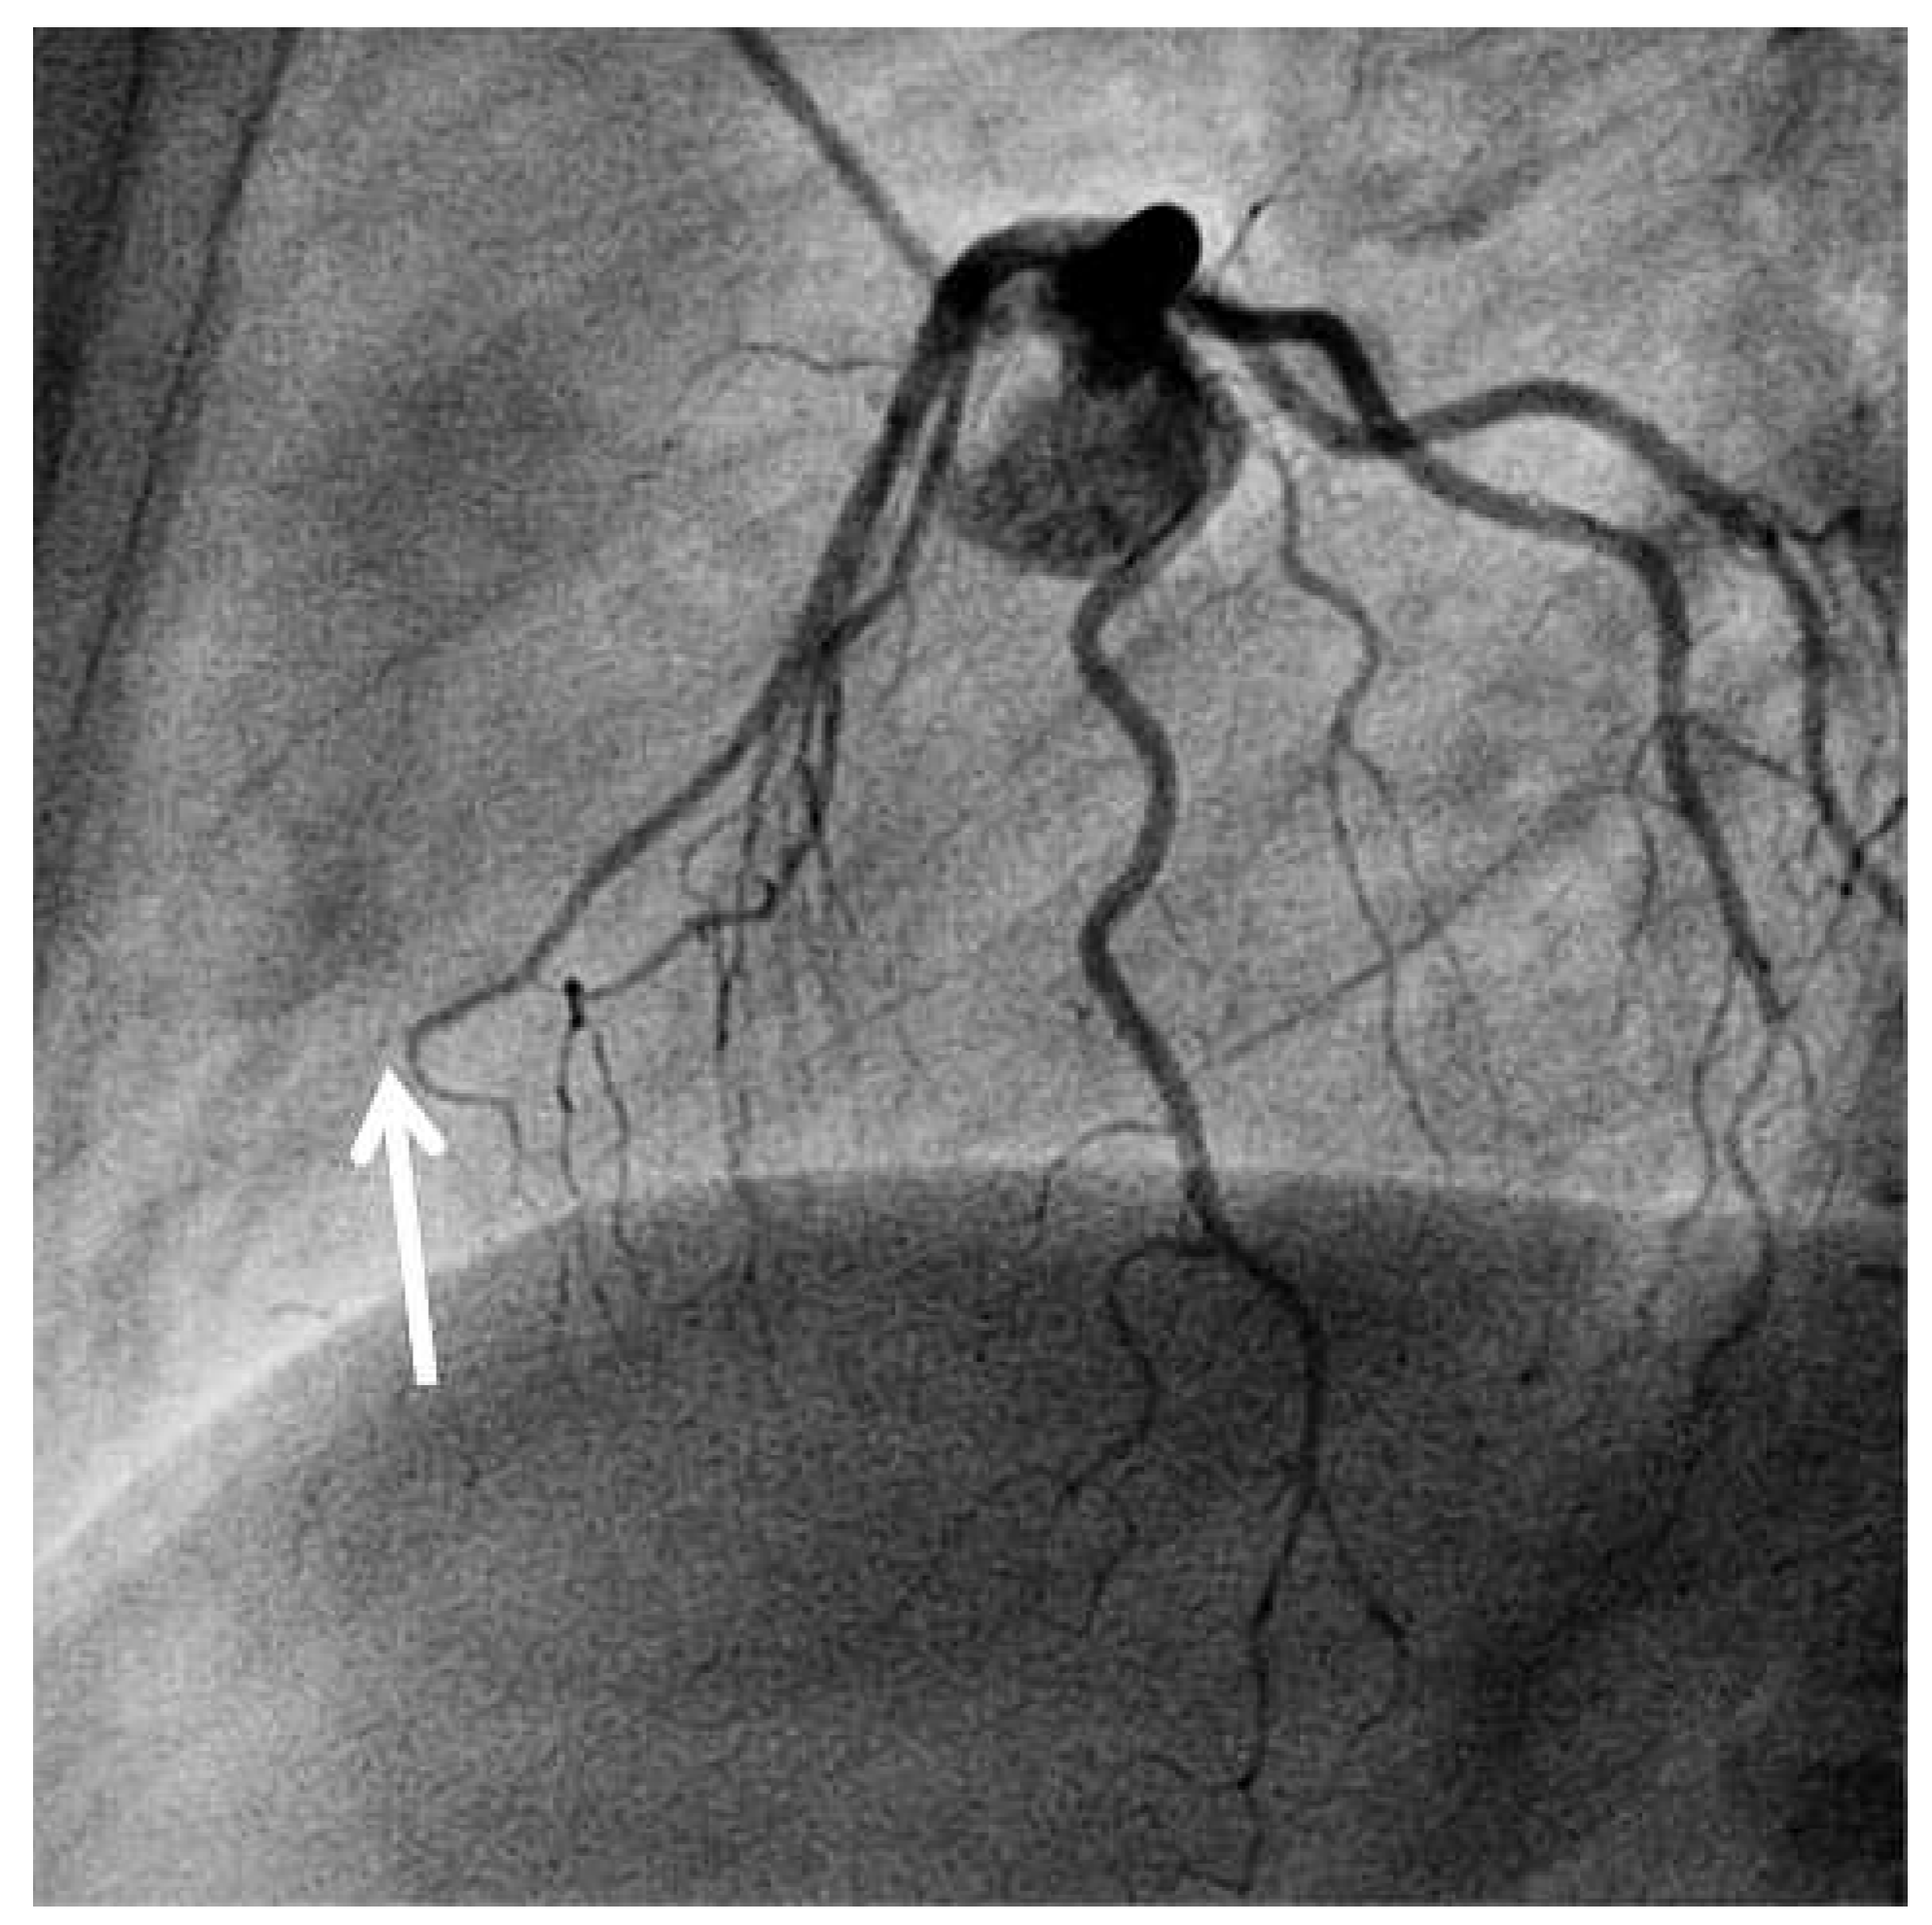

Left Ventricular Apical Thrombus Many Months After Pericardial Biopsy